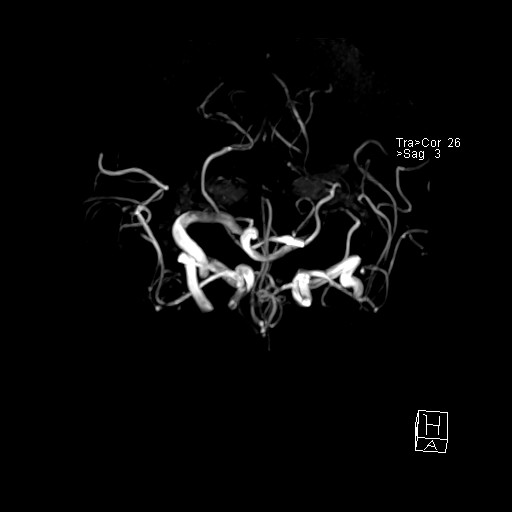

- VILLANUEVA, WILLIAM A. MR HEAD

- VILLANUEVA, WILLIAM A. MR HEAD

- VILLANUEVA, WILLIAM A. MR HEAD

- VILLANUEVA, WILLIAM A. MR HEAD

- VILLANUEVA, WILLIAM A. MR HEAD

- VILLANUEVA, WILLIAM A. MR HEAD

- VILLANUEVA, WILLIAM A. MR HEAD

- VILLANUEVA, WILLIAM A. MR HEAD

- VILLANUEVA, WILLIAM A. MR HEAD

- VILLANUEVA, WILLIAM A. MR HEAD

- VILLANUEVA, WILLIAM A. MR HEAD

- VILLANUEVA, WILLIAM A. MR HEAD

- VILLANUEVA, WILLIAM A. MR HEAD